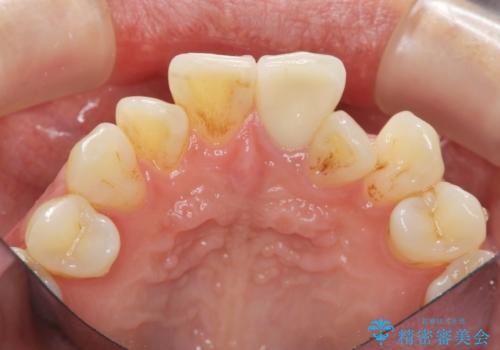

歯の変色 前歯の審美改善

- 前歯の変色の改善を求めて来院されました。

X線写真より、以前に神経の治療が為され変色をきたしている状態であることがわかりました。

根管内の感染は認められないのでセワミッククラウンの製作・装着を行い審美性を改善します。